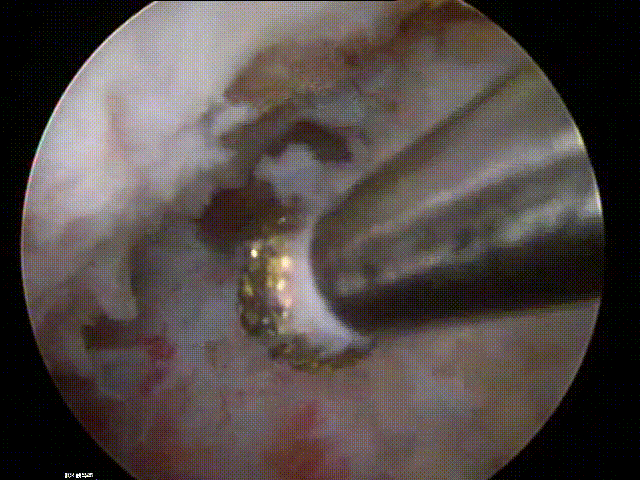

九、类脊髓高压综合征

病例

女,51岁。

主诉:腰疼伴左下肢疼痛麻木4个月。

既往史:椎间孔镜下椎间盘切除术(L4-5)。

术前

术中:术中硬膜破裂,灌洗液压力30mmHg,硬膜破裂后1小时出现血压升高,心率加快,手术持续2小时。

术后:延迟苏醒,拔管困难,转ICU,6小时候拔管神志恢复正常。

术后

思考与建议:

警惕硬膜损伤

全麻下早期表现:血压升高,心率加快

尽快结束手术或中转开放手术

有条件情况下给予硬膜修补

多数患者预后良好